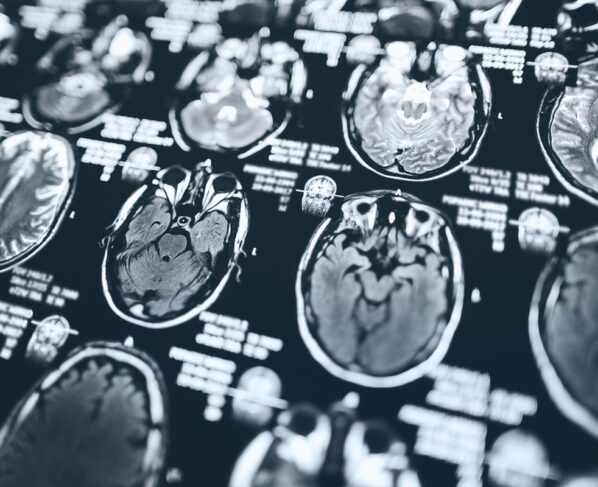

O medicamento, da empresa Eli Lilly, atua eliminando placas de beta-amiloide, proteínas que se acumulam no cérebro e estão associadas à perda de memória e declínio cognitivo.

- O Alzheimer é uma doença que afeta o funcionamento do cérebro de forma progressiva, prejudicando a memória e outras funções cognitivas.